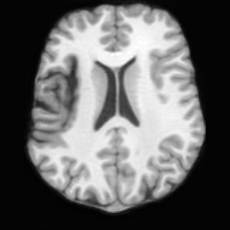

Healthy w/Lesion MaskPathologicalDifferencew/o LCGw/ LCG(a)Refer to captionRefer to captionRefer to captionRefer to captionRefer to captionRefer to captionHealthy w/Lesion MaskPathologicalDifferencew/o LCGw/ LCG(b)Refer to captionRefer to captionRefer to captionRefer to captionRefer to captionRefer to caption

Figure 7: Ablation study of Lesion Consistency Guidance (LCG). Without LCG, the generated pathological regions are indistinct and show weak pathological expression in both examples.

Lesion Consistency Guidance. Fig. 7 illustrates the impact of Lesion Consistency Guidance (LCG) for healthy-to-pathology editing. Without LCG, the generated lesion regions appear blurry around lesion boundaries, and the pathological patterns are less distinct, resulting in ambiguous lesion localization and weak pathological expression. Incorporating LCG produces lesions with more precise localization and well-defined shapes that better align with the given lesion masks, as well as textures and contrasts that exhibit stronger pathological characteristics. These results demonstrate that LCG effectively enforces lesion-aware conditioning, enhancing both spatial and semantic consistency of the generated pathological regions.